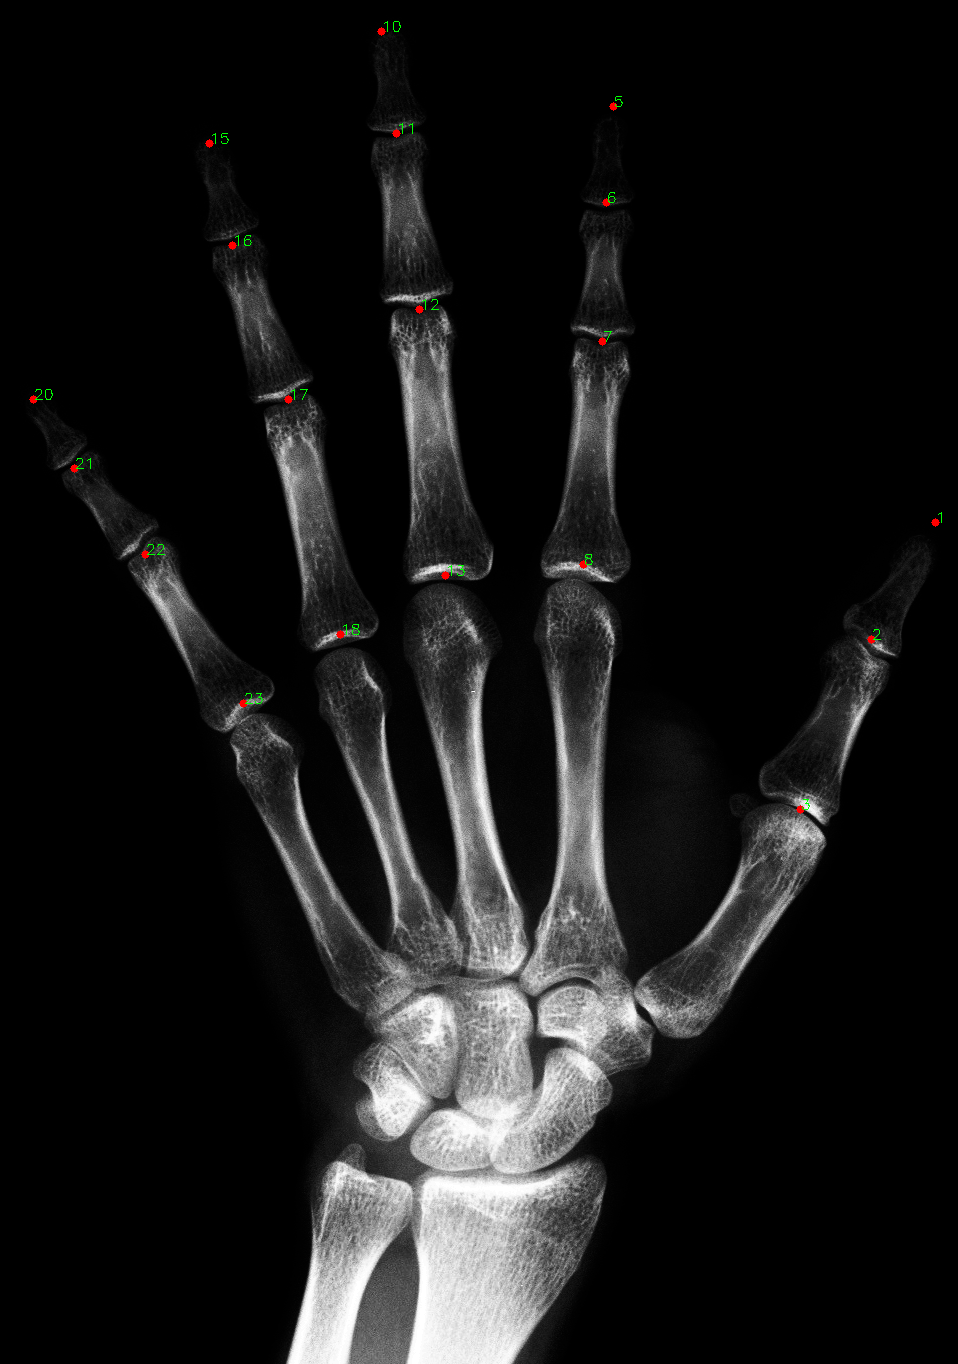

Labeling of finger landmarks in hand xrays.

Finger landmark labeling for left handed x-ray images

This project uses two algorithms (symbolic and neural) to extract finger landmarks from left hand x-rays. It's intended to be used as an auxiliary tool for forensics research at UNAM.

Note that the symbolic algorithm only approximates landmarks in four fingers (not including the metacarpophalangeal joints).